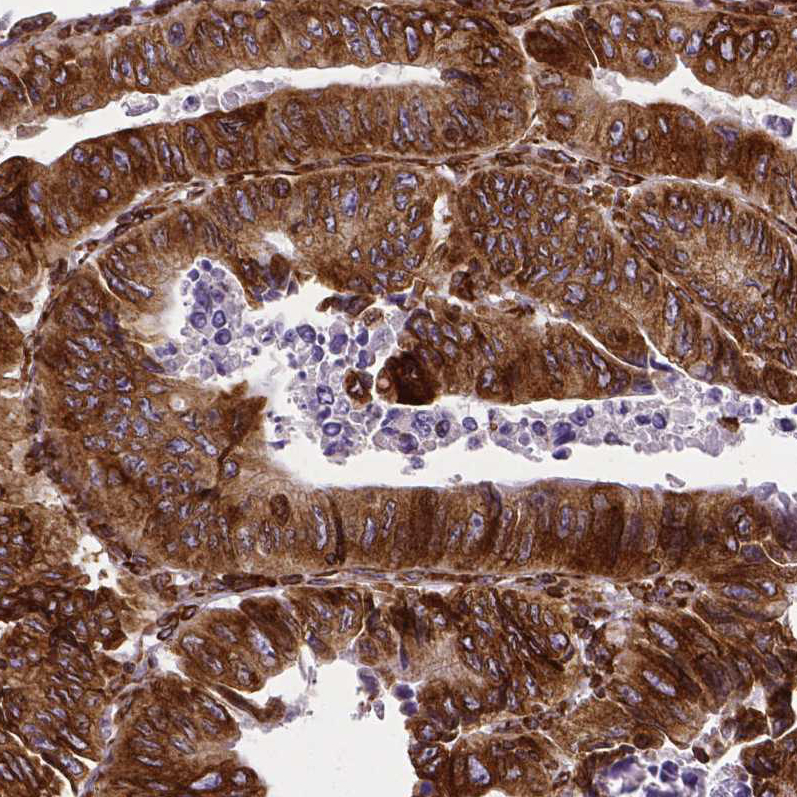

Immunohistochemical staining of human breast cancer shows strong cytoplasmic positivity in tumor cells.